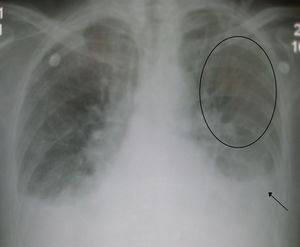

الجانب الأيسر هو المسؤول عن استقبال الدم المحمل بالأكسجين من أوردة الرئتين ثم ضخه إلى جميع أعضاءالجسم ومن ثم فالفشل في الجانب الأيسر يؤدي إلى تراكم الدم في الأوعية الدموية للرئتين والاحتقان فيهما فيؤدي إلى أعراض مرتبطة بيهما وقد يؤدي هذا التراكم أو الأحتقان إلى خروج السوائل من أوعية الرئتين إلى حجرات التنفيس، ويسبب وذمة الرئة. كما يؤدي فشل الجانب الايسر إلى فقر الدم الموزع إلى الأنسجة لفشله في ضخه لأعضاء الجسم فتعاني من نقص في أمداد تلك الأنسجة بالموادالغذائية والأكسجين. و أهم الأعراض هي:

علامات فشل الجانب الأيسر: ترتبط بفشل عمل القلب كمضخة وقلة الدم المضخوخ للأنسجة. مما يؤدي إلى ضعف النبض, هبوط في الضغط الانقباضي وزيادة سرعة ضربات القلب وبرودة الأطراف وقلة ادرار البول والشحوب. كما يرتبط قصور الجانب الايسر باحتقان الرئتين وتجمع السوائل فيهما.